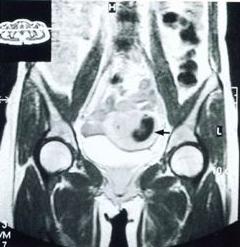

輸卵管膨出輔助診斷:陰道細胞學檢查楞協助診斷,如塗征中含不典型腺上皮纖毛細胞,提示有卵管膨出的可能。如找到膨出細胞,經分段診斷性刮宮排除宮頸癌和子宮內膜癌,宮腔吸液檢查。超聲檢查及腹腔鏡檢查增有助於診斷。

輸卵管膨出與卵巢腫瘤、輸卵管孵巢囊腫不易鑑別,如有可疑,宜及早沖腹探查確診之。

輸卵管膨出在超聲有能查出來的,主要是在輸卵管炎症的急性期,輸卵管的炎症造成傘端阻塞,炎症的滲出液積在輸卵管的管腔內使超聲顯示:子宮一側或雙側出現異常回聲輸卵管增粗,有的呈臘腸樣,管腔內呈低回聲或點狀回聲。